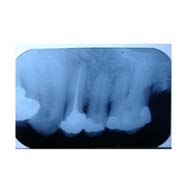

Root Canal Treatment (RCT) A tooth has three layers enamel, dentin and pulp. When the cavity is so deep that it reached the pulp, RCT has to be done.

In this all the infection from within the tooth is removed, all the canals in the root are cleaned and medicament is placed. The tooth is sealed so that no infection seeps in after RCT.

After performing RCT, the tooth becomes weak and brittle. That’s why post RCT crown is very important to protect the tooth.

Placing a crown helps the tooth to be strong and capable of withstanding the forces as in the normal tooth.

Root Canal inclusive of crown can be completed within 2 to 3 sittings.

What is the success rate of Rct? Root canal has a success rate of more than 95% thanks to the advanced materials available to perform the procedures today such as Apex locators and digital xrays to ensure accuracy; rotary instruments and fiber posts with core build up materials to improve the strength of tooth and CAD-CAM precision crowns bonded chemically to the tooth.